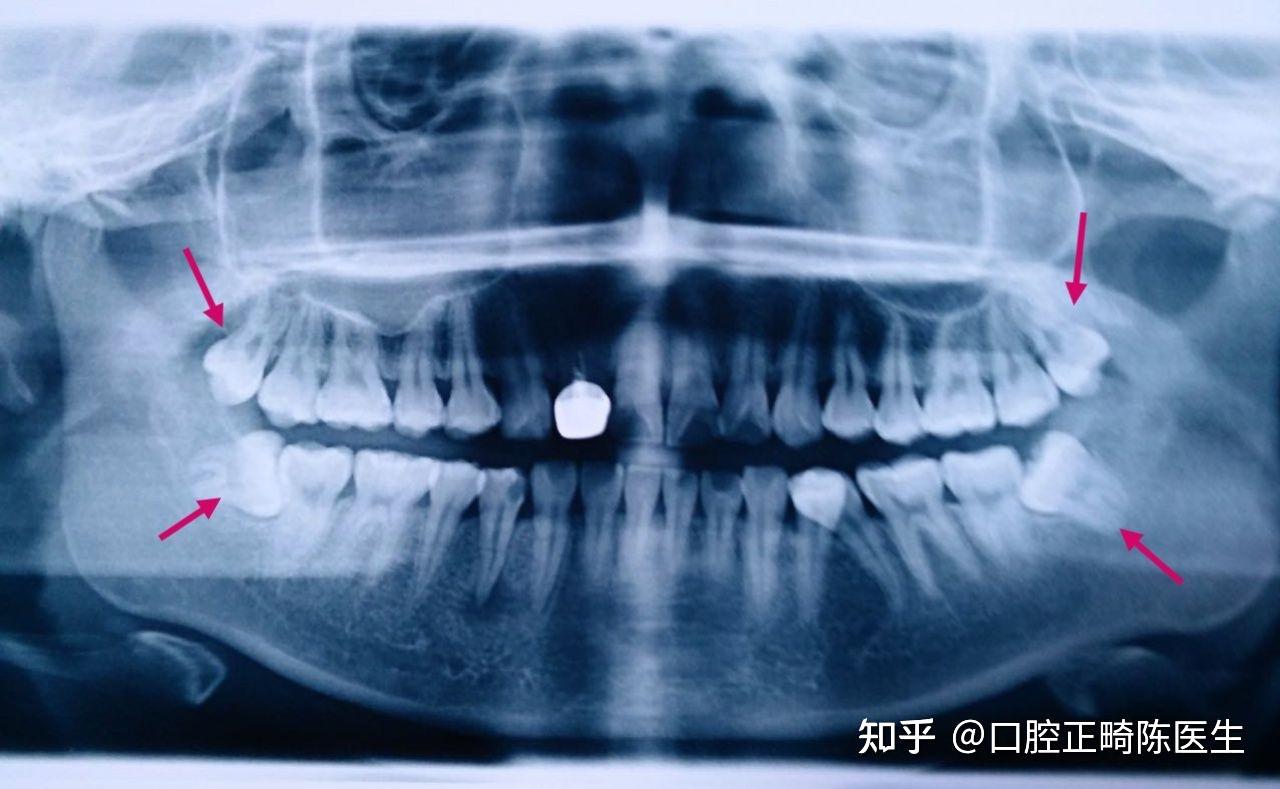

接下来,进行8颗牙的拔除(实际是拔了正畸牙只是4颗,还有4颗是长歪了的智齿,即使不做正畸,这四颗智齿也无法保留)。

每次看到自己的口腔全景片都自觉“年幼无知”没有好好处理保护自己的牙齿。